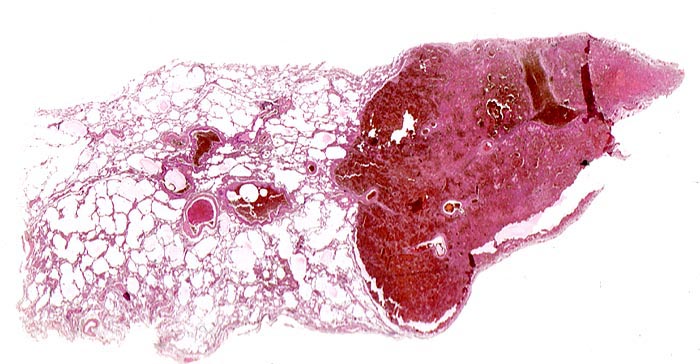

hämorrhagischer Lungeninfarkt

Frische blutdurchtränkte dreieckige Nekrosezone ohne Organisationszeichen in der Peripherie des Infarktes. Als Ursache für den Infarkt lässt sich im angrenzenden Lungenparenchym ein frischer Embolus in einem peripheren Lungenarterienast nachweisen. Auch dieser zeigt keine Organisationszeichen (kein Kontakt zwischen Gefässwand und Embolus).

Tiefe Beinvenenthrombosen bei metastasierendem Prostatakarzinom. Koronare Herzkrankheit.